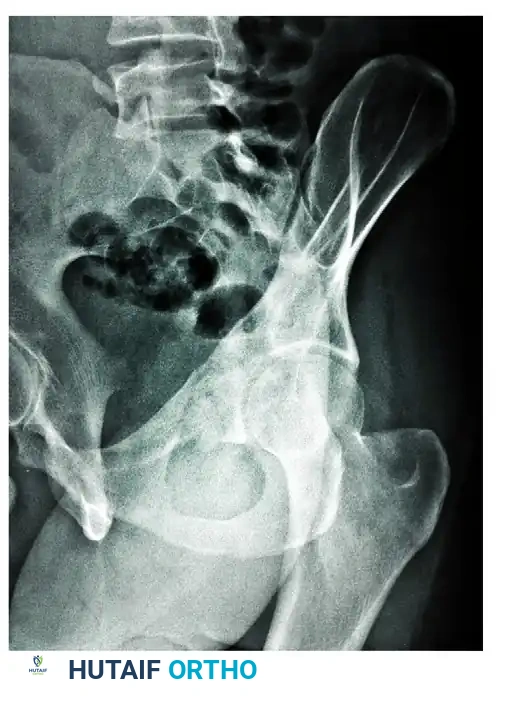

The Judet Oblique Views

To isolate the anterior and posterior columns, Judet and Letournel described two 45-degree oblique views. These are obtained by rolling the patient 45 degrees relative to the X-ray cassette.

The Iliac Oblique View

In the iliac oblique view, the patient is rolled 45 degrees toward the uninjured side (elevating the injured hip). The radiographic beam is directed roughly perpendicular to the iliac wing of the affected side.

* Primary Structures Visualized: This view places the iliac wing en face, providing an excellent profile of the posterior column and the anterior wall of the acetabulum.

* Diagnostic Utility: It is critical for identifying fractures traversing the sciatic notch, assessing the integrity of the posterior column, and evaluating anterior wall comminution.